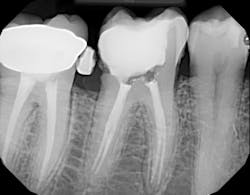

A tooth saved by typical nonsurgical root canal treatment. No peer-reviewed studies have shown this type of treatment being linked to cancer or heart attacks.